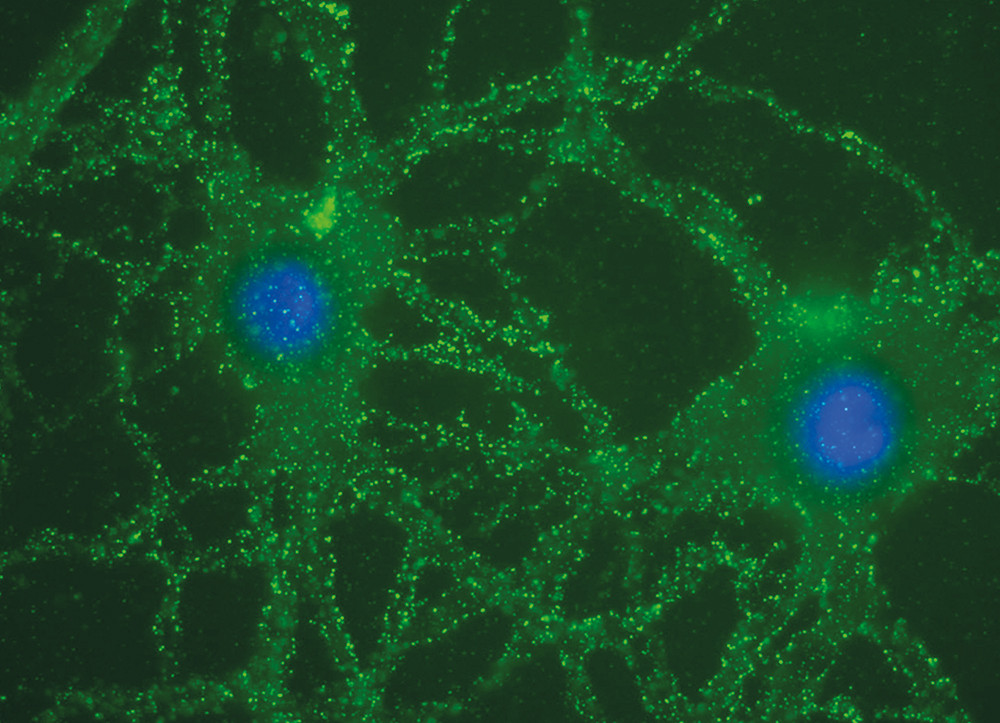

The obvious effect of plasma exchange clearly pointed towards an immune-mediated disease, but specific antibodies or other immunological markers could not be established while the patient was in hospital. Prior to the plasmapherisis, samples of the patient’s CSF and serum were frozen. In the light of reports of a new type of autoimmune encephalitis (7), the frozen samples were sent to the University of Pennsylvania, USA. The analyses showed the presence of NMDA (N-methyl D-aspartate) receptor antibodies in serum and CSF (Fig 2) (8), and we therefore concluded that the diagnosis was anti-NMDA receptor encephalitis.

Figure 3 illustrates the pathophysiological process in which antibodies block postsynaptic glutamatergic excitatory NMDA receptors (13). The clinical stages of the syndrome probably result from increasing antibody-mediated failure of NMDA receptor functions. The trigger factor for the formation of anti-NMDA receptor antibodies is associated with neoplasm in 60 % of cases; the remainder of cases are considered idiopathic (11).

The EEG pattern is almost always pathological and shows a slow rhythm combined with epileptic activity (14). As in the case of our patient (Fig 1), the rhythm change can occur relatively unilaterally (15). In the majority of cases, there are pathological findings in the CSF; these include a moderately increased leukocyte count and/or a slightly increased total protein level, and sometimes oligoclonal bands (11). MRI scans of the central nervous system show pathological changes in half the patients, and T2-weighted examination or FLAIR (fluid attenuated inversion recovery) examination can show modest hyperintensity in the temporal lobes, the cerebellum, the basal ganglia, the brain stem and sometimes the spinal cord (11). The diagnosis can be verified by findings of specific NMDA receptor antibodies in the CSF and serum. (Analyses are performed at Haukeland University Hospital’s neurology and rheumatology laboratory in Bergen.) Patients should be examined with a view to the presence of an underlying tumour. The incidence of neoplasm increases in patients over 18 years of age. In women, teratoma of the ovary is the most frequently associated tumour. Examinations relevant for patients with suspected anti-NMDA encephalitis are summarised in Box 2.